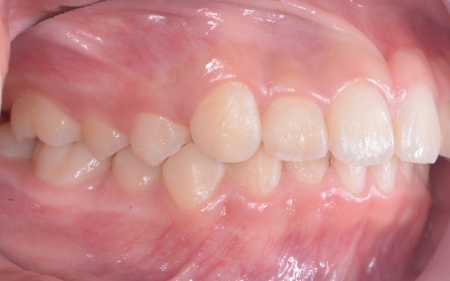

| カウンセリング | 拝見したところ、上の犬歯が歯列の外側に飛び出すように生えている、いわゆる八重歯でした。 さらに、上下の歯全体がデコボコに生えている「叢生(そうせい)」と呼ばれる状態で、これは歯が正しい位置に並ぶためのスペースが不足していることが原因だと考えられます。 このまま放置して顎の成長が完了してから矯正治療を行う場合、歯を並べるスペースを確保することが難しく、永久歯を抜く処置が必要になるケースがあります。 以上のことから、今の段階で歯並びを整える治療が必要だと診断しました。 |

患者様のご家族は「将来的な抜歯はできるだけ避けたいので、今のうちに治療をしたい」と希望されたため、成長期の段階で歯列を広げ、歯が並ぶスペースを確保する小児期の矯正治療「1期矯正」を提案しました。

メリット デメリット また、治療にあたりお口全体のバランスを確認したところ口元の突出はなく、顎のサイズはやや小さめですが、成長期であることから歯列の拡大が可能な状態だと判断しています。 以上の内容について丁寧に説明し、治療に同意いただきました。 まず、上顎に顎の骨を広げるための固定式の矯正器具「急速拡大装置」を、下顎には歯並びの幅を広げるための「リンガルアーチ」を装着します。 次に歯の位置を整えるため、ワイヤー矯正を開始します。 最後に、歯並びが整って見た目や噛み合わせにも問題がないことを確認し、装置を取り外して第1期矯正治療を終了しました。 現在も経過観察を継続していますが、歯が元の位置に戻る後戻りも見られず、残っている乳歯から永久歯への生え変わりも順調に進んでいます。 |